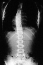

- XRAYS: A 24 degree left thoracic curve from T5 - Tl1

was noted on scoliosis spine films.With the asymmetric abdominal reflexes

and high thoracic left curve she was sent for an MRI scan. This revealed

a large syringomyelia with dilatation in the lower cervical and upper thoracic

area. Also noted was an Arnold-Chiari malformation.